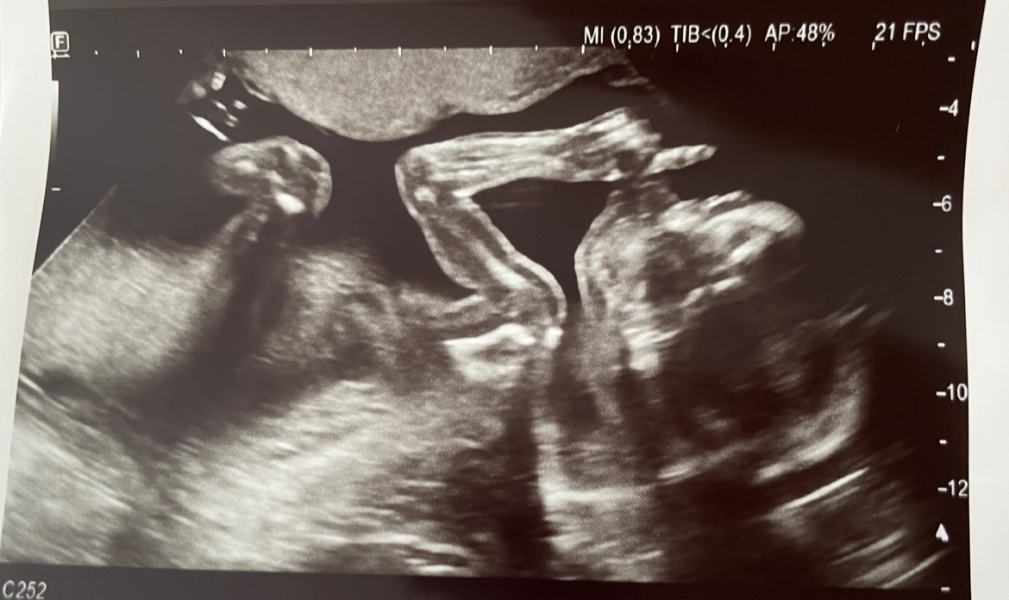

BabyD6 · 30/10/2023 15:02

Had my 20 week scan today (I am 20+5). Baby all good and growing perfectly. Thought I’d post my scan photo here as made us giggle. Looks like the baby is telling me to be quiet 🙊 Also looks like baby has big biceps haha!

@Busylizzie85 How did your scan go?

@BabyD6 that's such a fab scan photo. Haha I love the 'shh' pose , so cute

@BabyD6 Your scan is amazing! Love it 😆 Mine's on Thursday.

@BabyD6 thats such a great scan photo!